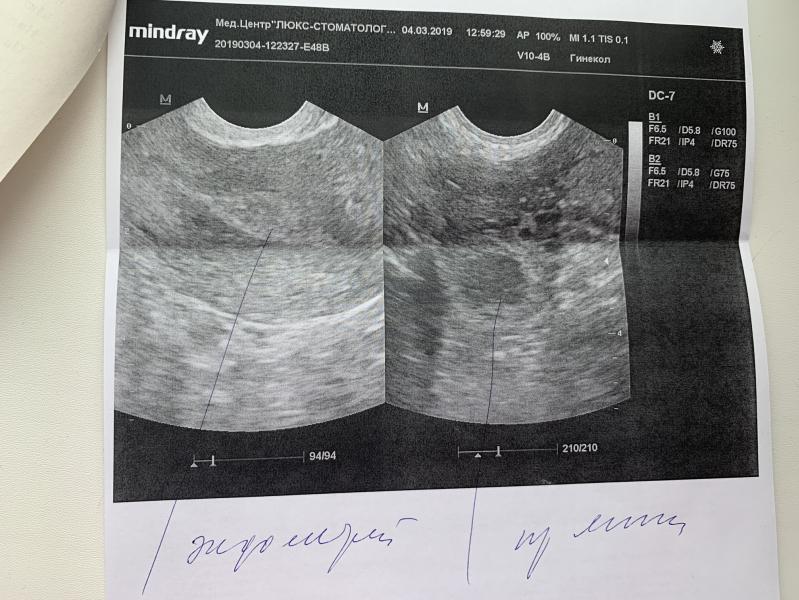

Девочки, я уже совсем запуталась😞 посмотрите пожалуйста, на узи не смогли понять ЖТ это или доминантный фолликул🤷🏼♀️ стараться ещё или нет уже, день Х 6марта..

Овуляцию определяют по наличию жт и свободной жидкости, у вас похоже уже была О)

По мне больше похоже на желтое тело, у фолликула обычно более чёткие границы. Но на вашем месте я бы продолжала стараться😅

Это жт